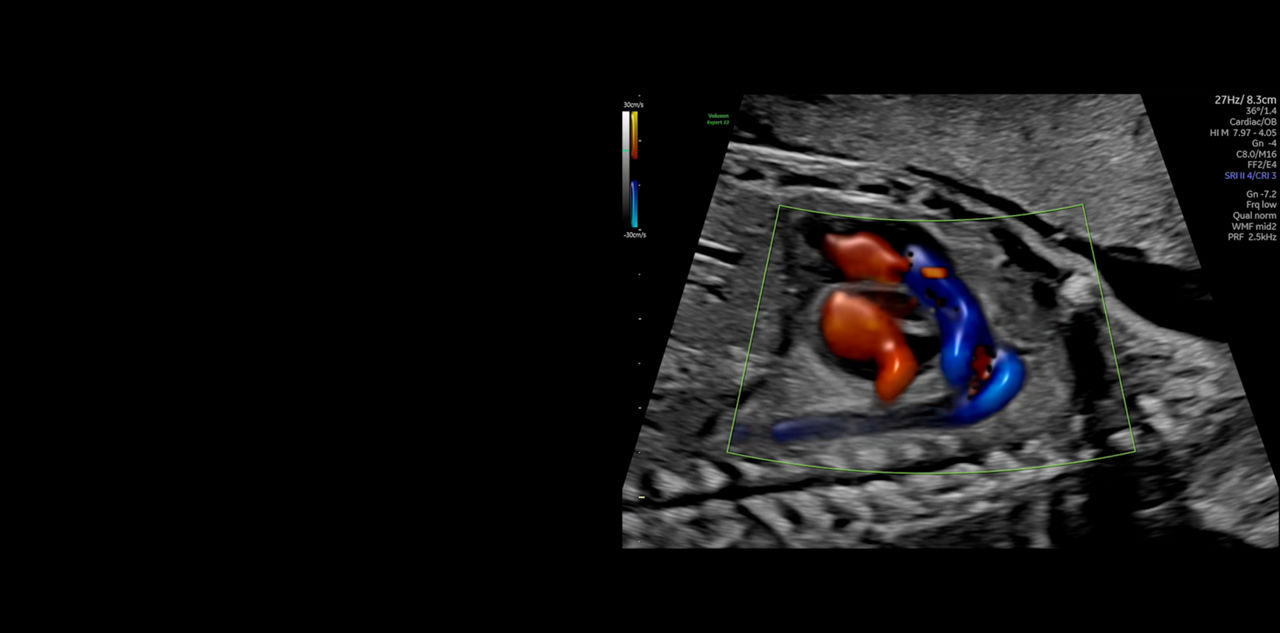

FETAL HEART EVALUATION

Get to the Heart of the Matter

Identifying fetal cardiac abnormalities earlier means you can intervene sooner, plan for delivery, and potentially improve outcomes. The Voluson Expert 22 provides a full solution of progressive tools, to help distinguish the tiniest structures with stunning clarity to provide patient answers faster.